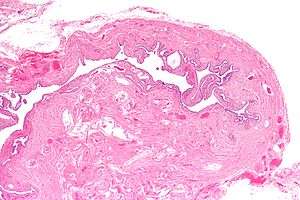

| Micrograph of salpingitis isthmica nodosa, showing the characteristic nodular thickening. H&E stain. | |

Salpingitis isthmica nodosa, also known as diverticulosis of the Fallopian tube, is nodular thickening of the narrow part of the uterine tube, due to inflammation. It is abbreviated SIN.

It is characterized by nodular thickening of the tunica muscularis of the narrow (isthmic) portion of the Fallopian tube. In severe cases, it leads to complete obliteration of the tubal lumen. It is uncommonly bilateral.[2]